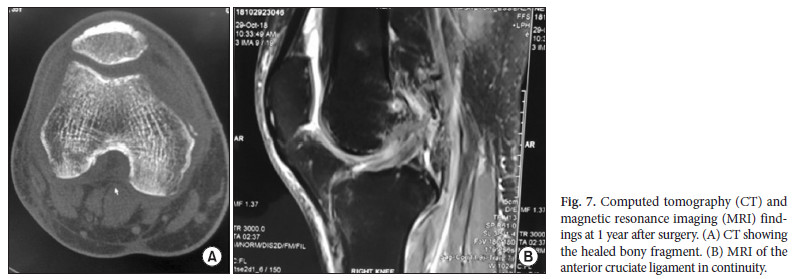

La tomodensitométrie et l'IRM ont été effectuées trois mois après l'opération. Ils ont révélé que le LCA était en continuité et le fragment osseux consolidé (Fig. 7). Le ML et le LCM apparaissaient complètement guéris à l'IRM. À trois mois et à un an après l'opération, le genou était stable, le test du tiroir antérieur négatif et le test de stress du valgus également. À un an du suivi, le patient avait une EVA=0 et avait repris le sport et ses loisirs.

La tomodensitométrie et l'IRM ont été effectuées trois mois après l'opération. Ils ont révélé que le LCA était en continuité et le fragment osseux consolidé (Fig. 7). Le ML et le LCM apparaissaient complètement guéris à l'IRM. À trois mois et à un an après l'opération, le genou était stable, le test du tiroir antérieur négatif et le test de stress du valgus également. À un an du suivi, le patient avait une EVA=0 et avait repris le sport et ses loisirs.